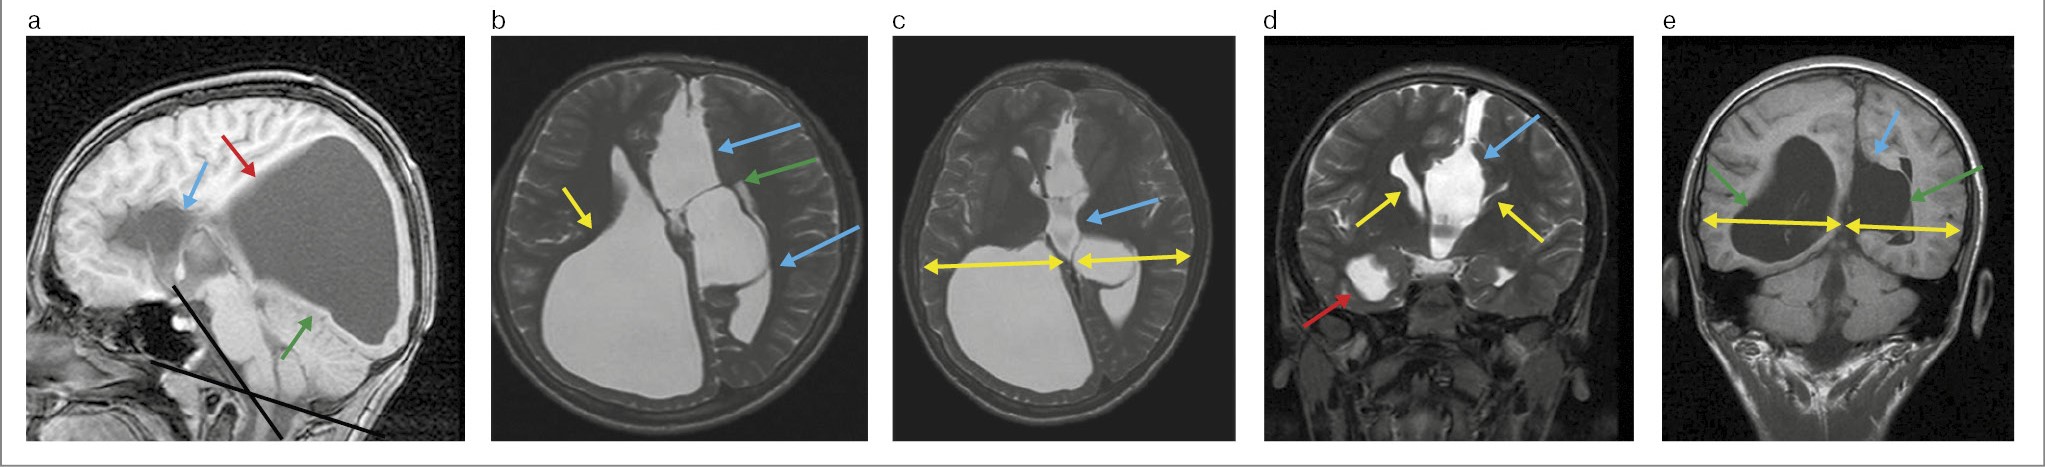

Выполнена МРТ ГМ с контрастированием. На серии Т1–Т2-взвешенных томограмм в сагиттальной, аксиальной и коронарной проекциях получены изображения ГМ. Отмечается асимметрия полушарий большого мозга D>S, на уровне дна III желудочка размеры составляют: справа – 73 мм, слева – 67 мм, дорсальнее асимметрия более выражена. МТ и прозрачная перегородка в сагиттальной проекции не визуализируются. Межполушарно в вентральных отделах определяется жидкостное образование размером 101×34×77 мм, компримирует латеральные желудочки. Высокое расположение III желудочка по типу «шлема викинга».

В правой височно-теменно-затылочной области имеется жидкостное образование, связанное с полостью правого латерального желудочка, размером 77×62×84 мм. Определяется аномальная поясная извилина. Визуализируются миелинизированные пучки Пробста. Гиппокамп закруглен на аксиальных срезах. Угол Богарта 140°. Хиазмальная область без особенностей, гипофиз в размерах не увеличен.

Заключение: МРТ-картина полной АМТ и прозрачной перегородки. Межполушарная менингеальная киста типа 2a. Порэнцефалическая киста правой височно-теменно-затылочной области. Признаки платибазии (рис. 1).

Рис. 1. Больной Ф., 11 лет. МРТ ГМ: a – Т1-взвешенное последовательное изображение в сагиттальной плоскости: полное отсутствие МТ (голубая стрелка); аномальная поясная извилина (красная стрелка); порэнцефалическая киста (зеленая стрелка); угол Богарта 140° (черные линии); b – Т2-взвешенное последовательное изображение в аксиальной плоскости: межполушарная менингеальная киста (голубые стрелки); перегородка межполушарной менингеальной кисты (зеленая стрелка); порэнцефалическая киста (оранжевая стрелка); c – Т2-взвешенное последовательное изображение в аксиальной плоскости: размеры полушарий большого мозга на уровне III желудочка, справа – 73 мм, слева – 67 мм – наибольшее измерение (желтые стрелки), тело III желудочка (голубая стрелка); d – Т2-взвешенное последовательное изображение в коронарной плоскости: межполушарная менингеальная киста (голубая стрелка); порэнцефалическая киста (красная стрелка); вертикально расположенные передние рога латеральных желудочков мозга – симптом «шлем викинга» (желтые стрелки); e – Т1-взвешенное последовательное изображение в коронарной плоскости: межполушарная менингеальная киста (голубая стрелка); латеральные желудочки мозга (зеленые стрелки); асимметрия полушарий большого мозга (желтые стрелки).